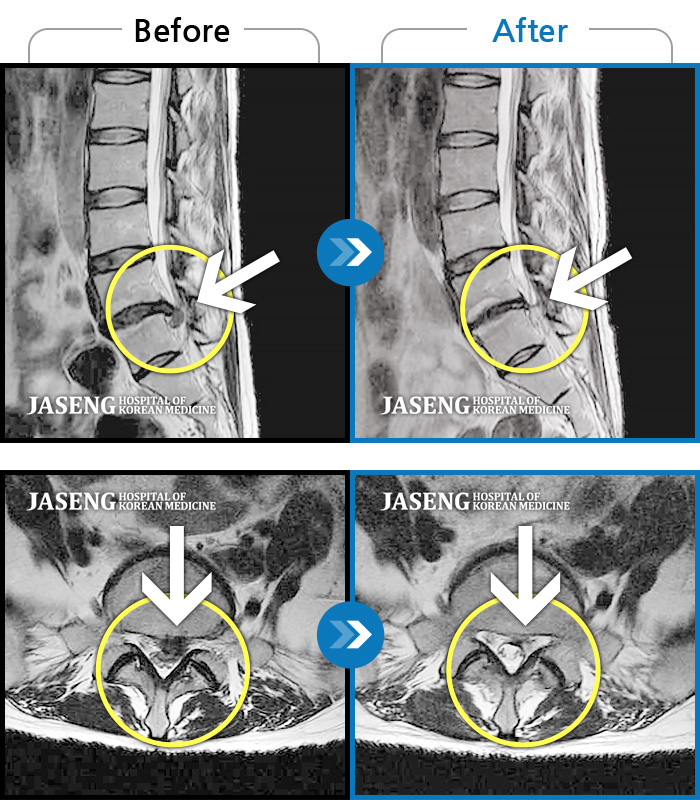

원장님 친절 하게 상담 해 주시고 아픈 곳 진료를 잘 해 주셔서 참 감사드립니다 척추치료에는 이순호 원장님 최고 입니다 수술 하지 않고도 정성껏 실력 있습니다

목 디스크 치료 완료하였습니다.계획보다 일찍완치되어 기쁘고요